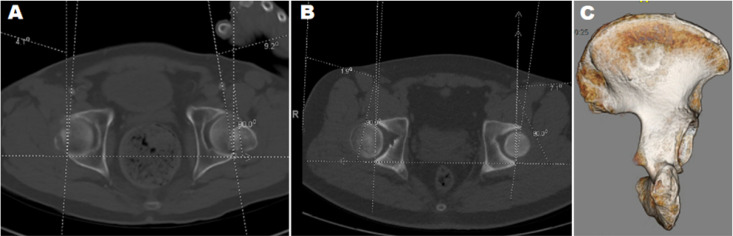

Purpose: There is limited evidence regarding the outcomes of hip hemiarthroplasty (HA) following trauma in individuals living with Down syndrome (DS). This study aims to summarize the outcomes of hip HA in a series of individuals living with DS following femoral neck fractures.

Materials and methods: This retrospective study includes five cases of hip HA in four individuals with DS and displaced femoral neck fractures. Subjects (four males) had a mean age of 49.3 years (range, 26.1-59.7 years) at the time of surgery. All subjects presented with hip pain, loss of weight-bearing ability, and decreased activity level as reported by the subject caregivers. In all cases, the precise time of injury was not known.